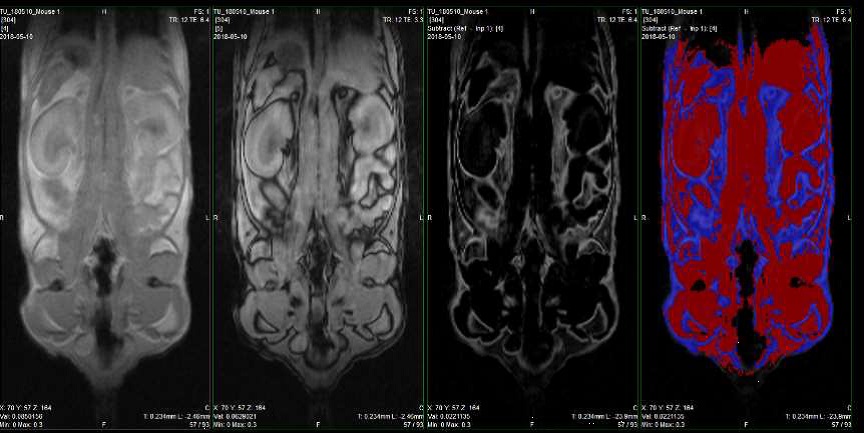

:脂肪、:軟組織

(老齢マウス)

(若齢マウス)

老齢マウス 若齢マウス

右後肢体積(mm3) 1024.63 1054.39

左後肢体積(mm3) 1018.26 1104.19